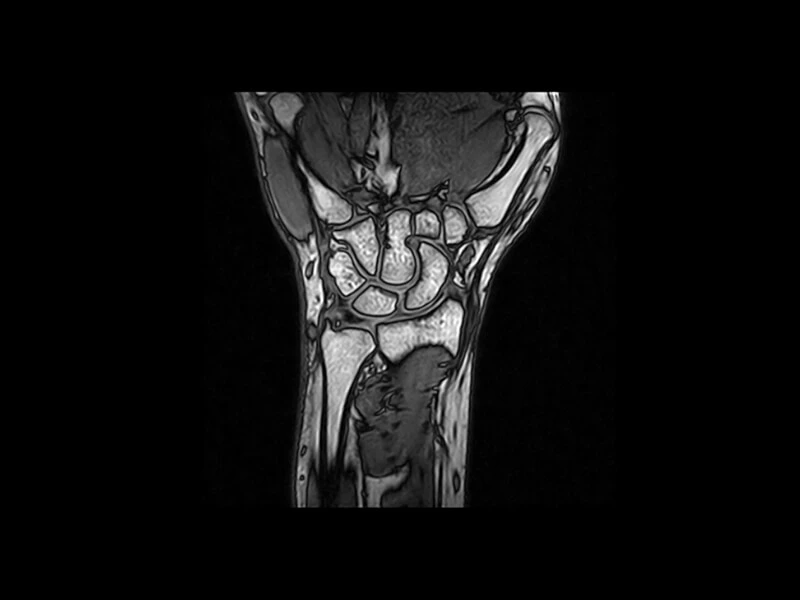

G-scan OPEN je novi MRI sistem kompanije Esaote koji omogućava proučavanje svih zglobova, kao i kičme, bilo u klinostatičnom (ležećem) ili ortostatičnom (opterećenom) položaju, jer se magnet i pacijent mogu rotirati od 0 do 90 stepeni.

KLINIČKE SLIKE